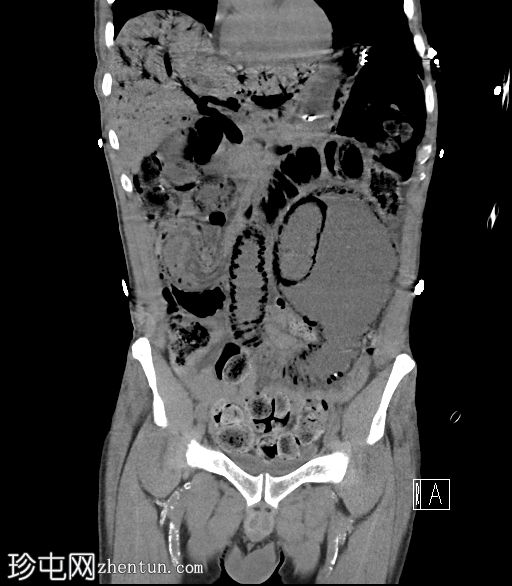

CT

冠状位片

平扫

门静脉积气。胃管末端位于胃底。下腹部可见长段小肠套叠,套叠起始点位于右下腹。伴有远端小肠广泛积气,左下腹肠段扩张,最符合小肠梗阻和缺血的表现,可能由长段小肠套叠引起。

门静脉积气通常预后不良,但该患者最终存活并出院。当肝脏内出现气体时,鉴别诊断包括胆道积气(胆道积气)和门静脉积气。通常区分并不困难:胆道积气聚集在肝脏中央,方向与胆汁流动方向一致;而门静脉积气则位于肝脏外周,方向与门静脉血流方向一致(由中央向外周)。